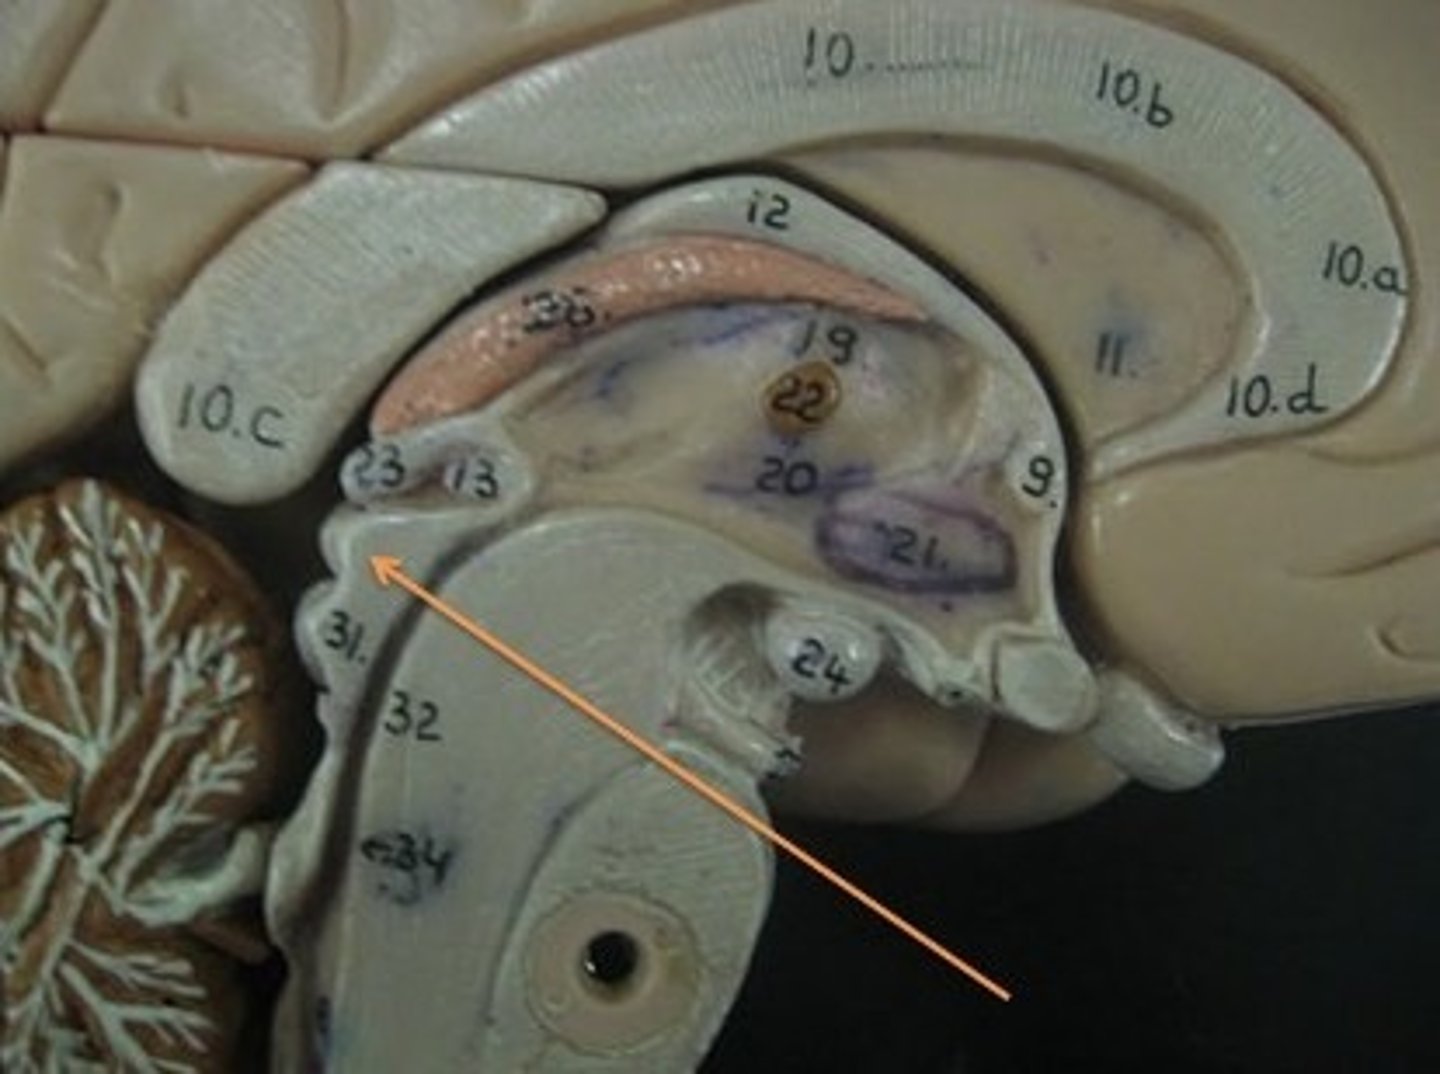

brain stem

Includes the mid brain, pons, and medulla oblongata.

midbrain

corpora quadrigemina,connector of cerebrum, diencephalon, and cerebellum to spinal cord. Connector in central nervous system.

corpora quadrigemina

Also known as the tectal plate. Consists of the superior colliculi and the inferior colliculi.

superior colliculi

bumby part on opposite side of pituitary gland. Top one. Responsible for visual reflex (track objects visually). If we see something in peripheray, we can turn towards object. Instinctive reflex.

inferior colliculi

bumpy part on opposite of pituitary gland. Bottom one. 31 auditory tracking. If we hear a loud noise, we can move toward it.

pons

contains parts of respiratory center. Plays a role in controlling breathing rate and depth.

medulla oblongata

has a cardiac center. Plays a role in influencing heart rate and the force of the contractions in the heart. In response to changes in blood pressure and oxygen levels.

- vasomotor center - helps to control blood pressure. Sends out signals that causes vasoconstriction or vasodilation of blood vessels. Contains parts of respiratory center.

- initiates inspiration and respiration.

cerebellum

cerebellar hemispheres, cerebellar cortex, and arbor vitae.-

the little brain.

- Function: coordinates all voluntary movements. Ability to ride a bike, dance, anything complicated that calls for coordinating movement between left and right sides with skeletal muscles.

- Ability to move joints in a coordinated fashion- cerebellum in charge.

cerebellar hemispheres

divided by vermis.

cerebellar cortex

outer covering of cerebellum - gray matter.

arbor vitae

"tree of life" white matter in cerebellum.

ventricles

cavities in the brain. Includes lateral ventricles - right and left, third ventricle, fourth ventricle, cerebral aqueduct, and choroid plexus.

third ventricle

in the area where the hypothalamus is.

fourth ventricle

located beneath the arbor vitae in the cerebellum.

cerebral aqueduct

connector between third and fourth ventricle in front of colliculi.